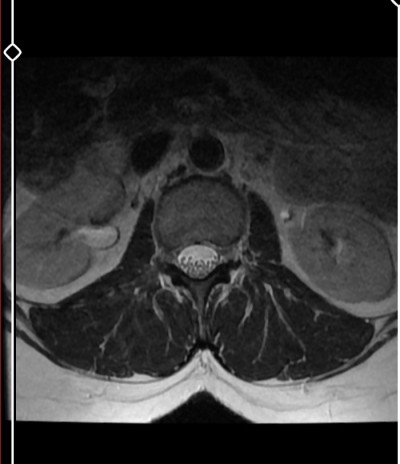

image

yarin sonuca gideceğim ama bilen varmı ?